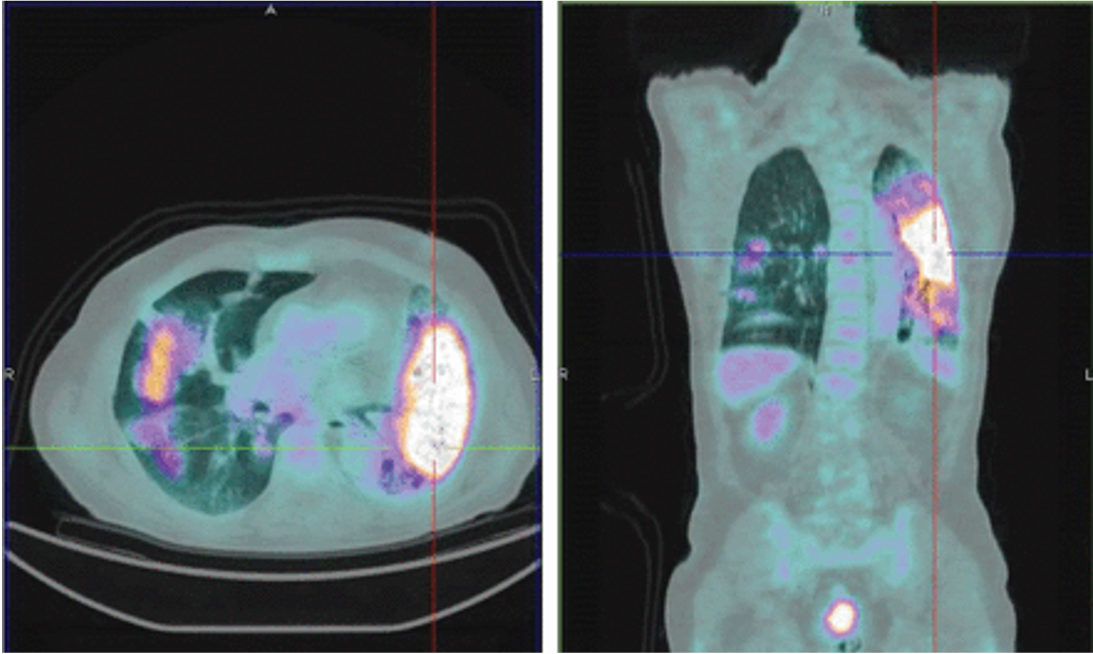

The following PET image is indicative of:

A diffuse infection